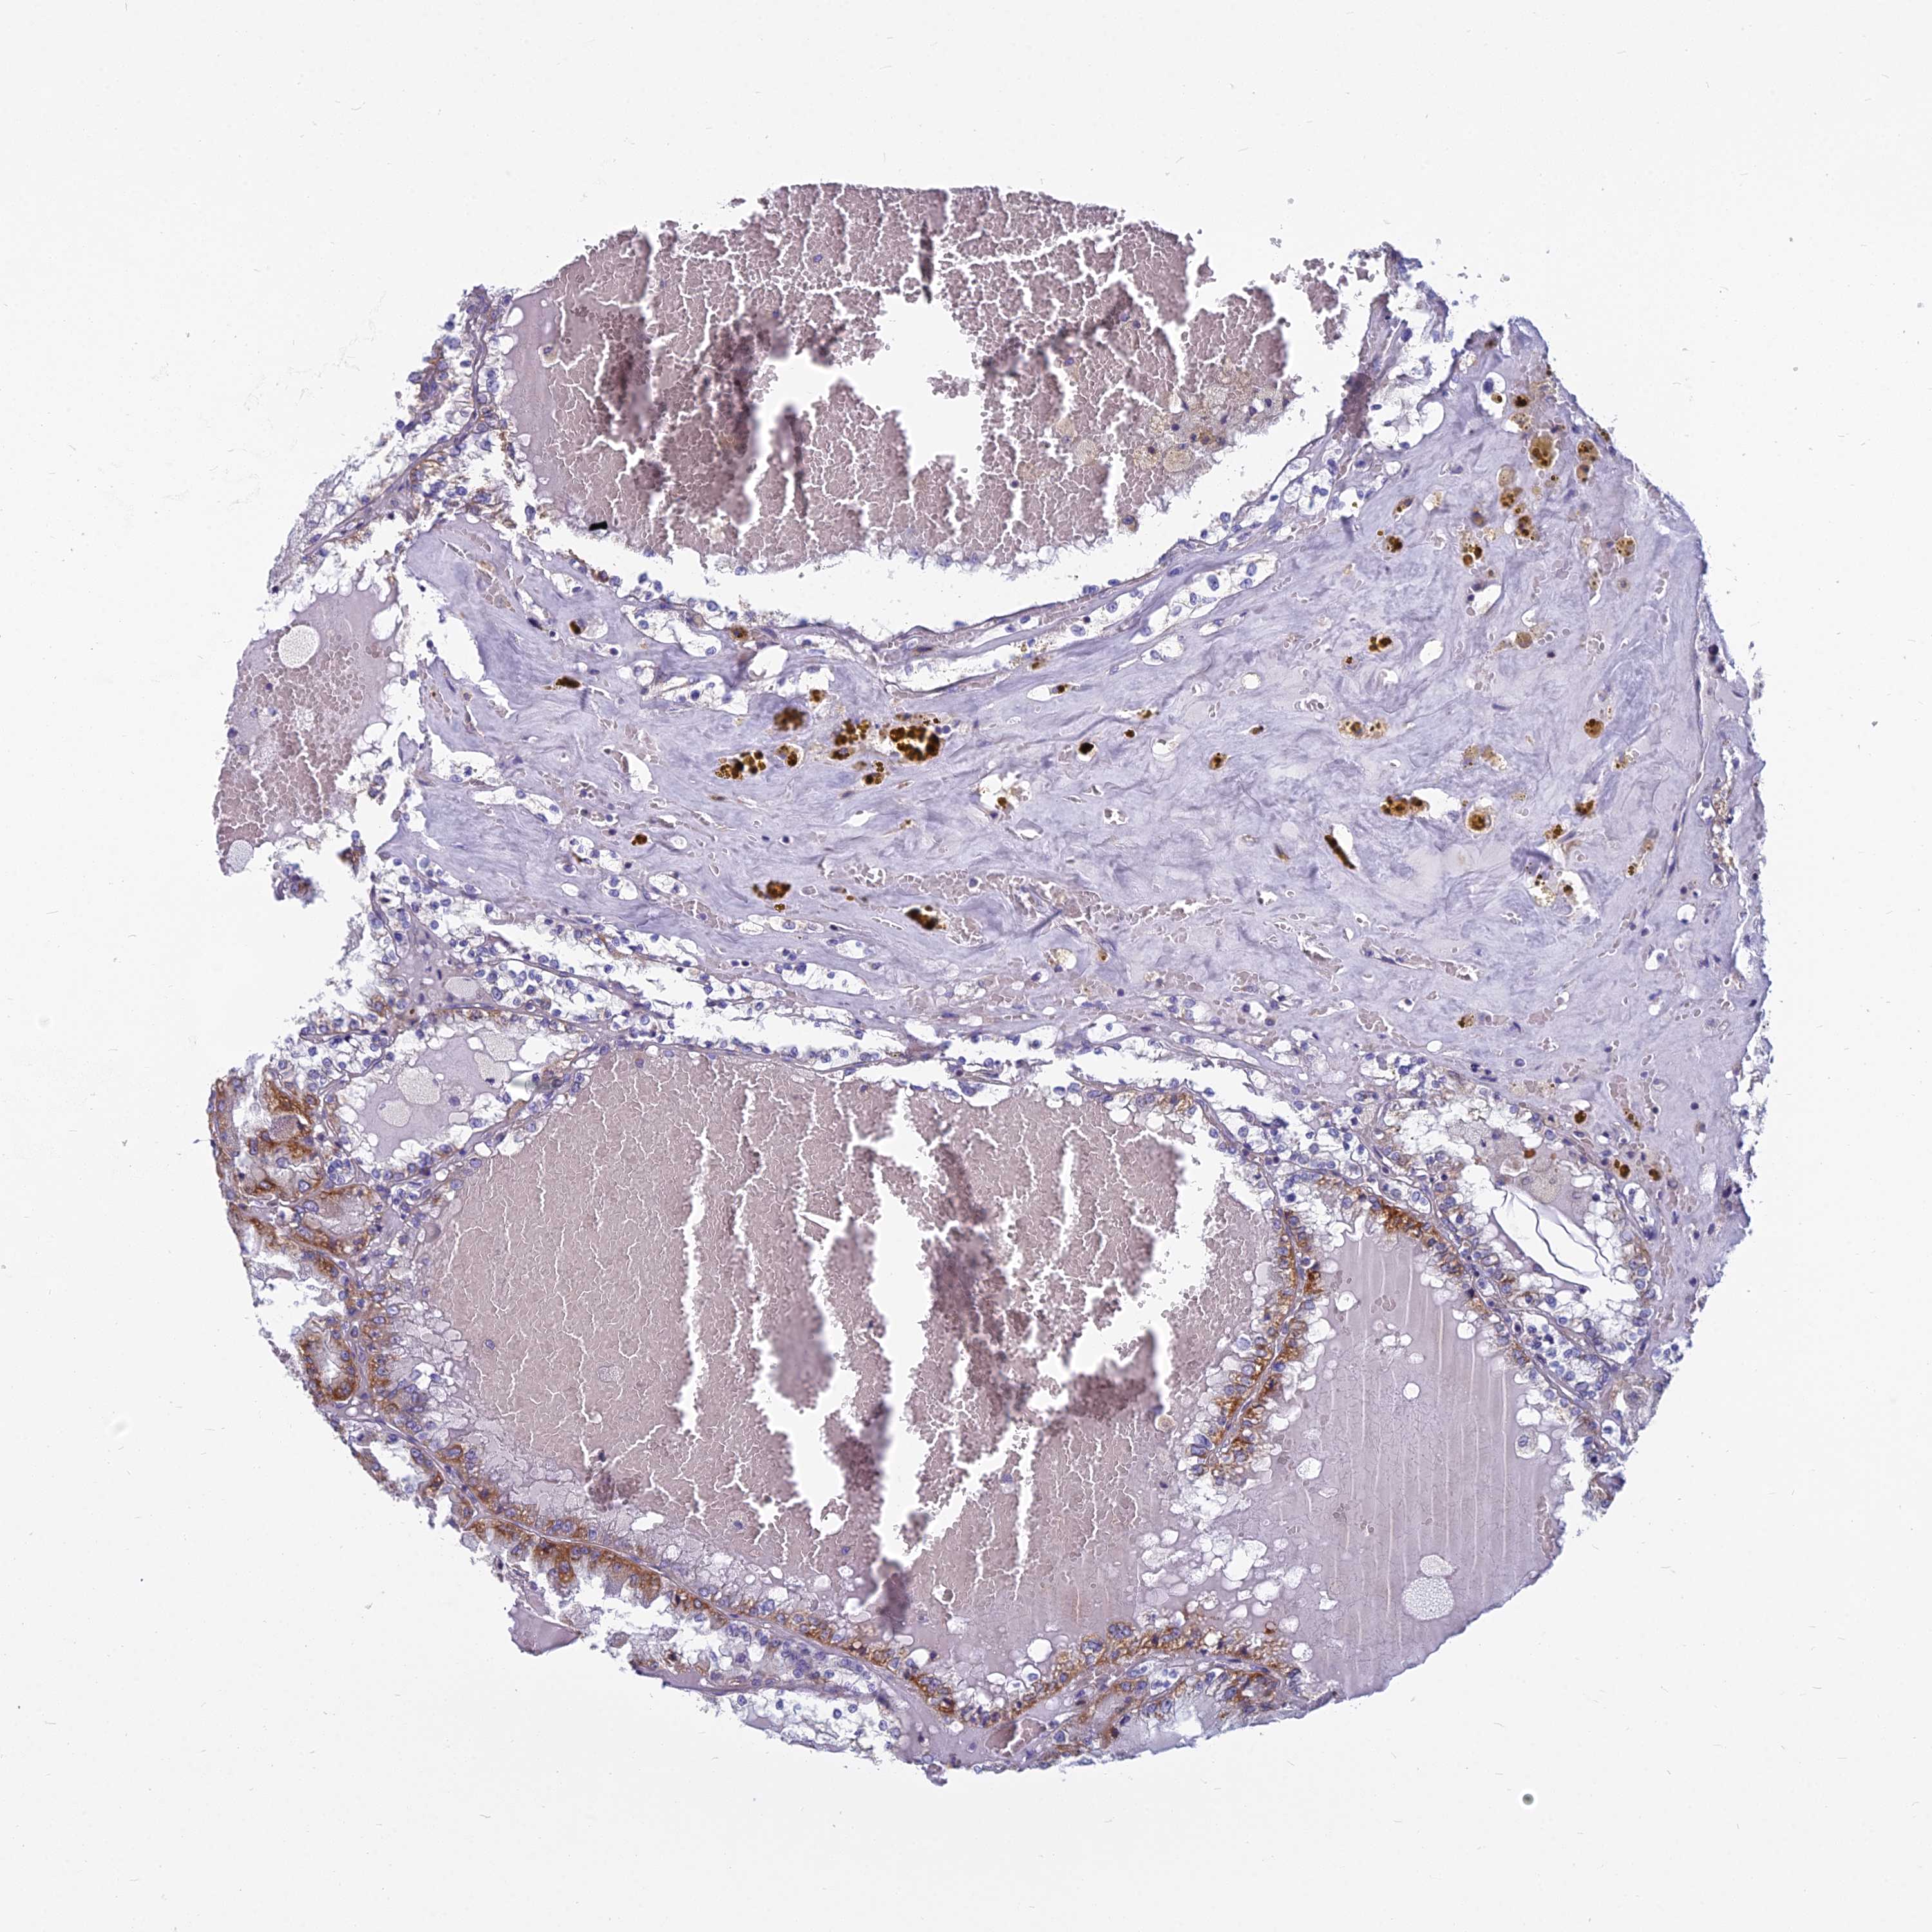

KIDNEY RENAL CLEAR CELL CARCINOMA (VALIDATION) - Interactive survival scatter ploti

The Survival Scatter plot shows the clinical status (i.e. dead or alive) for all individuals in the patient cohort, based on the same data that underlies the corresponding Kaplan-Meier plots. Patients that are alive at last time for follow-up are shown in blue and patients who have died during the study are shown in red.

The x-axis shows the expression levels (FPKM) of the investigated gene in the tumor tissue at the time of diagnosis. The y-axis shows the follow-up time after diagnosis (years). Both axes are complimented with kernel density curves demonstrating the data density over the axes. The top density plot shows the expression levels (FPKM) distribution among dead (red) and alive patients (blue). The right density plot shows the data density of the survived years of dead patients with high and low expression levels respectively, stratified using the cutoff indicated by the vertical dashed line through the Survival Scatter plot. This cutoff is automatically defined based on the FPKM cutoff that minimizes the p-score. The cutoff can be changed by dragging the vertical line or by entering a cutoff value in the square labeled "Current cut-off".

Under the Survival Scatter plot the p-score landscape (black curve; left axis) is shown together with dead median separation (red curve; right axis). Dead median separation is the difference in median mRNA expression between patients who have died with high and low expression, respectively. It is calculated as follows: median FPKM expression of dead patients with high expression - median FPKM expression of dead patients with low expression. This is intended to aid the user in visually exploring custom cutoffs and the associated p-scores and dead median separation.

Individual patient data is displayed and can be filtered by clicking on one or more of the category buttons on the top of the page. Categories describing expression level and patient information include: high, low, alive, dead, female, male and tumor stages. The scale of the x-axis can be toggled between linear and log-scale by clicking on the "x log" button. Mouse-over function shows TCGA ID, patient information and mRNA expression (FPKM) for each patient.

& Survival analysisi

Kaplan-Meier plots summarize results from analysis of correlation between mRNA expression level and patient survival. Patients were divided based on level of expression into one of the two groups "low" (under cut off) or "high" (over cut off). X-axis shows time for survival (years) and y-axis shows the probability of survival, where 1.0 corresponds to 100 percent.

COX20 is not prognostic in Kidney Renal Clear Cell Carcinoma (validation)

Best expression cut offi

: 35.26

TCGA RNA samplesi

RNA-seq data is reported as average FPKM (number Fragments Per Kilobase of exon per Million reads), generated by the The Cancer Genome Atlas (TCGA) .

Normal distribution across the dataset is visualized with box plots, shown as median and 25th and 75th percentiles. Points are displayed as outliers if they are above or below 1.5 times the interquartile range. FPKM values of the individual samples are presented next to the box plot.

Average pTPM 49.8

Number of samples 100